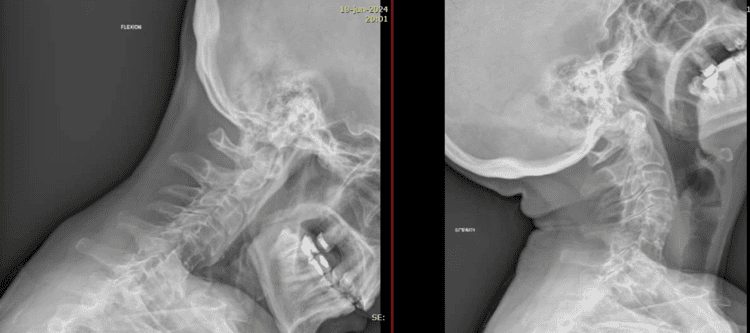

Radiografías simples

Las radiografías simples son a menudo el primer paso en las pruebas de imagen. Permiten observar la estructura ósea de la columna cervical. A través de estas imágenes se pueden detectar deformidades, desplazamientos vertebrales y otros problemas óseos que puedan estar causando el dolor.